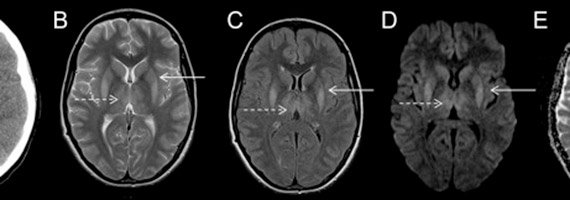

Computed tomography ct scanners have increased from a single slice detector to advanced 320 slice scanners capable of performing whole head imaging in a single rotation. Imaging in anaesthesia and critical care gregory j hobbs ravi p. Frost mount sinai medical center new york new york dr.

Ultrasound has a role in vascular access in neural access for nerve blocks and regional anesthesia transesophageal echocardiography tee for cardiac imaging with blood flows and to assess the depth of epidural space in cases of difficult anatomy. The anaesthetic and critical care implications of these interventions are described.